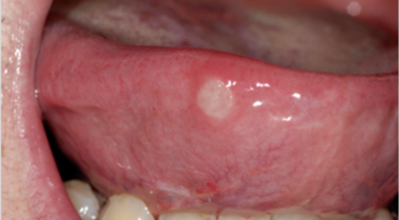

입안 점막이 동그랗게 패여 통증을 유발한다면, 아프타성 구내염을 의심할 수 있어요. 음식을 먹을 때마다 아픈 작은 궤양이 생겼다면, 아프타성 구내염을 의심할 수 있어요. 아프타성 구내염은 빨간색 둘레를 가진 둥근 형태의 흰색 궤양이, 얕은 깊이로 한 개 및 여러 개 생기며 통증을 동반하는 것이 특징입니다. 전 인구의 20~40%가 발병할만큼 통상적으로 나타나는 질환으로 20대, 주로 여성분들에게 많이 나타나며, 일주일 정도면 자연적으로 치유되지만 1~3개월 간격으로 빈번히 재발하는 것이 특징입니다.